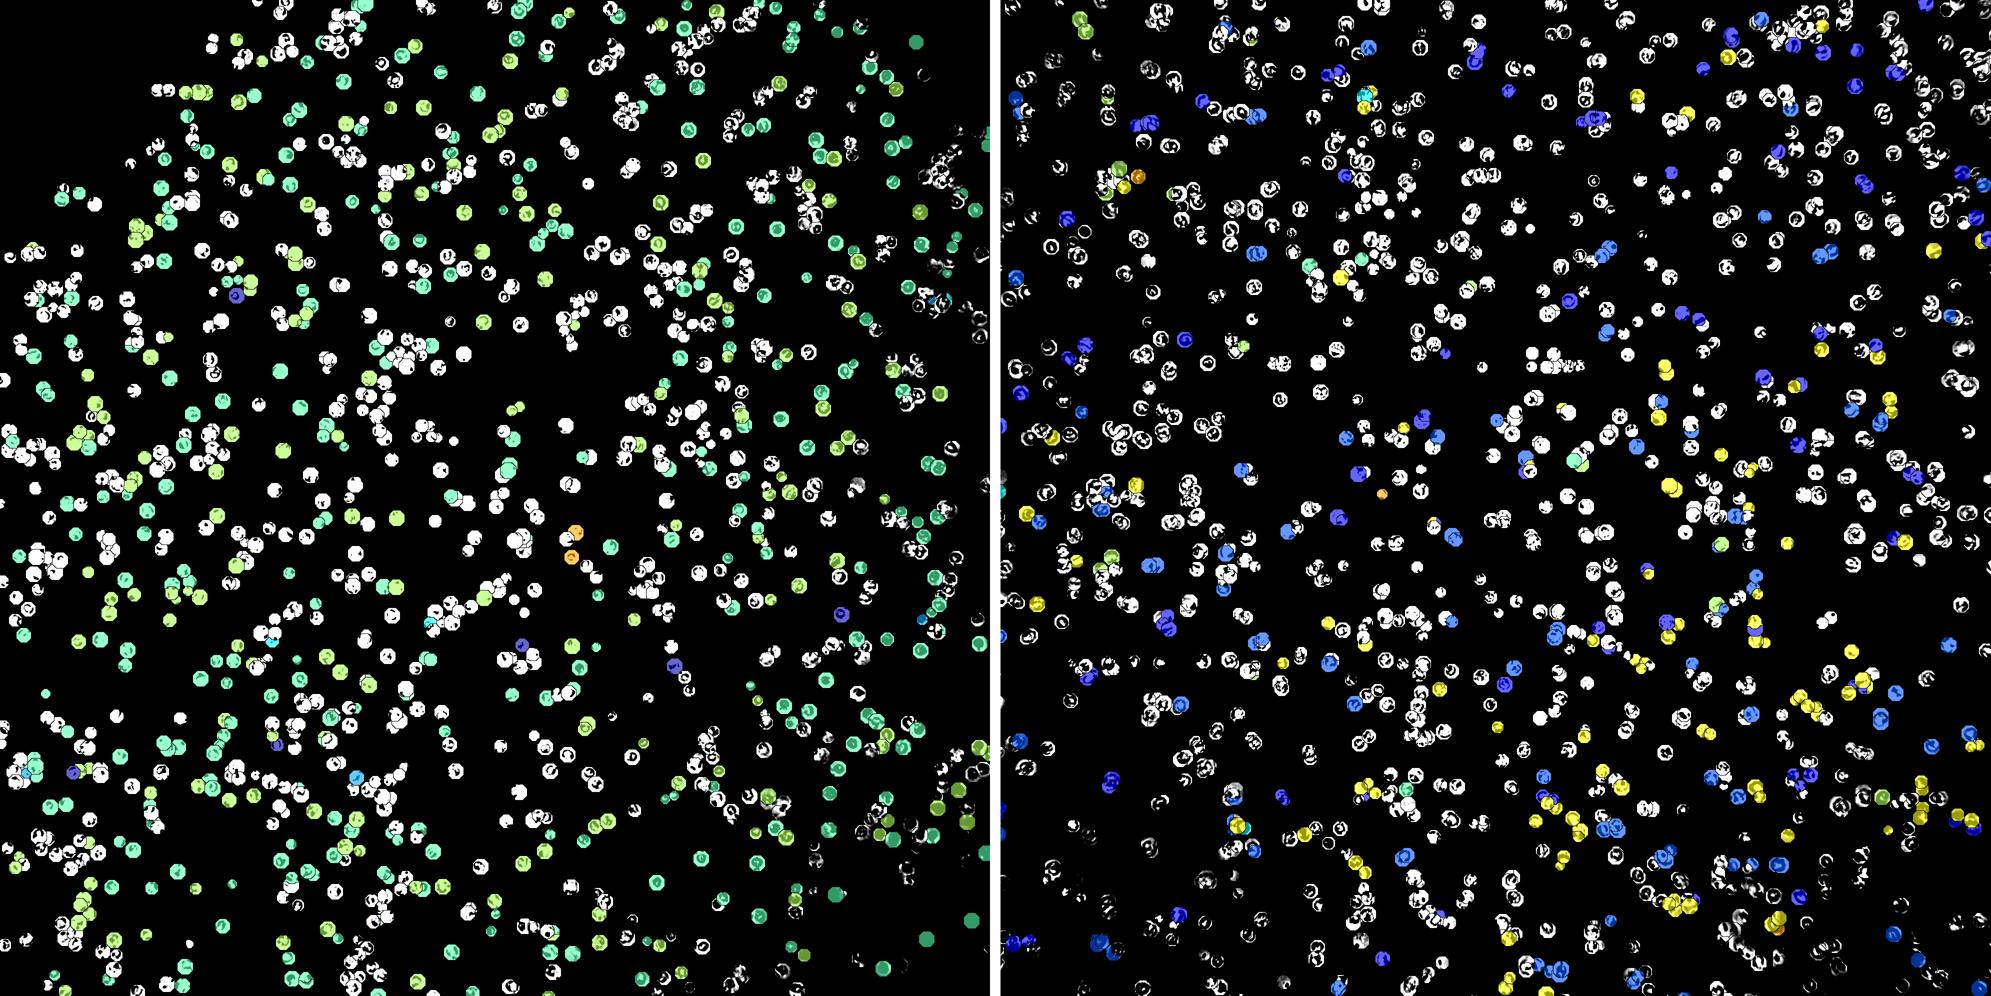

Cells labelled with CD15 CD8a

Peripheral blood lymphocytes

Inflammatory Disease

Cell populations before and after treatment